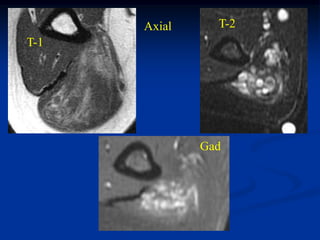

CLASSIC     Case #285         Sagittal T-1 MRI

67 year female with myxoid liposarcoma knee

Myxoid Liposarcoma The myxoid variant is the most common variant of the lipo- sarcoma and it is seen in a slightly younger age group between 40 and 50 years of age. It occurs in the lower extremities in 75% of cases, especially in the popliteal area. These lesions are slow growing and frequently asymptomatic in the early stages. On imaging studies, the MRI is the best method for visualizing these tumors that will have a mixed high and low signal on the T-1 weighted image because of the high percentage of fatty tissue in the tumor. Histologically, there will be evidence of malignant lipoblasts and it is common to find a plexiform network of small capillary tubes running thru the fatty tumor, similar to the capillary hemangioma. The prognosis for this variant is quite good after a wide local surgical resection, followed in most cases by local radiation therapy. The chance of pulmonary metastases runs as high as 20% and occasionally there will be multifocal myxoid

liposarcomas occurring inthe extremities as well as in retro- peritoneal locations. Occasionally, one will see a transitional form of myxoid converting into a higher grade round cell lipo- sarcoma which carries a more guarded prognosis.

CLASSIC Case #285 Sagittal T-1 MRI 67 year female with myxoid liposarcoma knee